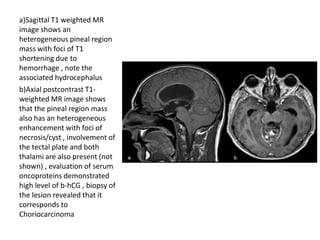

a)Sagittal T1 weighted MR

image shows an

heterogeneous pineal region

mass with foci of T1

shortening due to

hemorrhage , note the

associated hydrocephalus

b)Axial postcontrast T1-

weighted MR image shows

that the pineal region mass

also has an heterogeneous

enhancement with foci of

necrosis/cyst , involvement of

the tectal plate and both

thalami are also present (not

shown) , evaluation of serum

oncoproteins demonstrated

high level of b-hCG , biopsy of

the lesion revealed that it

corresponds to

Choriocarcinoma